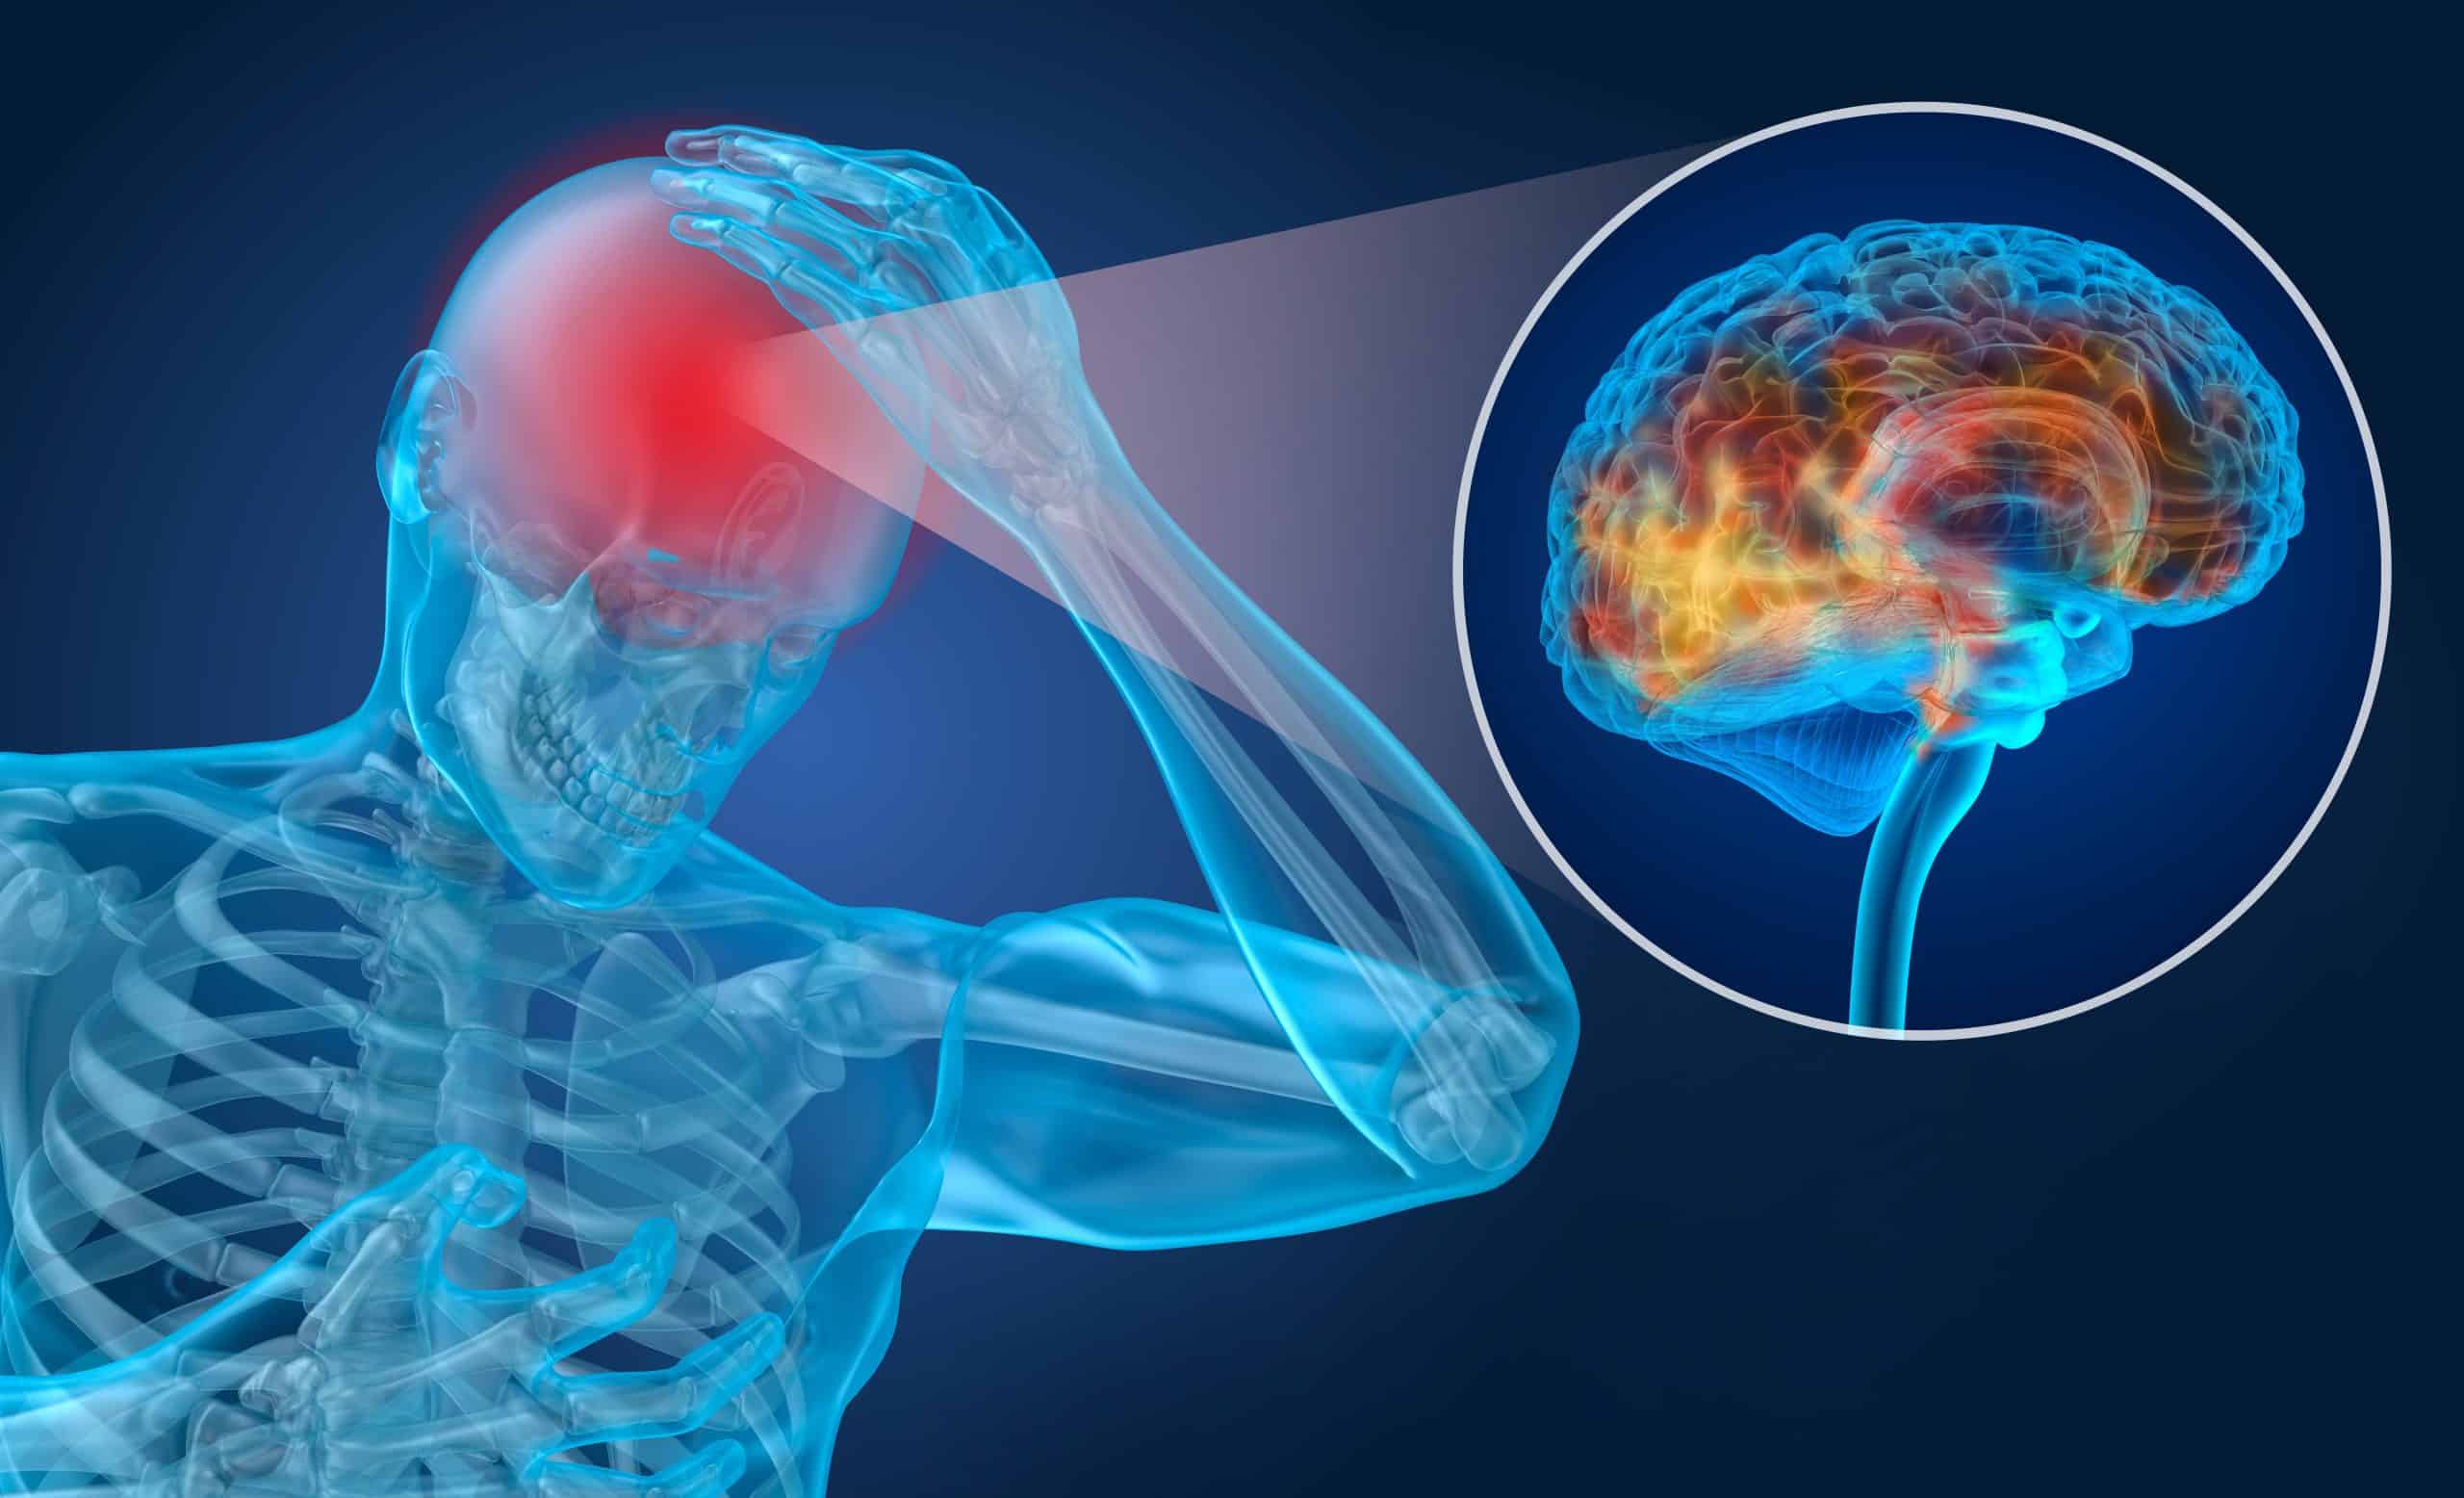

टाउकोमा अचानक लाग्ने चोट हो ट्रमाटिक ब्रेन इन्जुरी (टीबीआइ) । यसलाई हेड इन्जुरी पनि भनिन्छ । सवारी दुर्घटना, खेल खेल्दा लागेको चोट, हिंसा, विस्फोटक व्लाष्ट आदिले टाउकोमा लाग्ने चोट ट्रमाटिक ब्रेन इन्जुरी हो । स्ट्रोक, ट्युमर, एन्युरिजम, न्युरोलोजिकल समस्या, संक्रमण आदि कारणले ब्रेनलाई गराउने इन्जुरी नन ट्रमाटिक ब्रेन इन्जरी हुन् ।

टाउकोमा लागेको चोटले व्यक्तिको सोच्ने क्षमतालाई असर गर्नसक्छ । साथै ट्रमाटिक ब्रेन इन्जुरी घातक पनि हुनसक्छ । कतिपय व्यक्ति कोमामा समेत पुगेका हुन्छन् ।

दिमागको झिल्ली बाहिर चोट लागेमा त्यो एक्स्ट्राड्युरल हेमाटोमा हो । भित्र भएमा सबड्युरल हेमाटोमा भनिन्छ । यसलाई रगत जमाउने हेमाटोमा पनि भनिन्छ । गिदीमा चोट लागेर थिलथिलो भएमा त्यसलाई कन्ट्युजन भनिन्छ । वास्तवमा ब्रेन सामान्य पिठोको डल्लो जस्तै हुन्छ । तर त्यसमा माइक्रोस्कोपिक रूपमा धेरै तारहरू हुन्छन् । चोट लाग्दा ति तार (एक्जन) हल्लिएमा डिफ्युजन एक्जोनल इन्जुरी हुने गर्छ ।

टाउकोमा चोट लागेर रगत जम्ने समस्या प्राइमरी ब्रेन इन्जुरी हो । रगत जमेपछि दिमागलाई थिच्दै मस्तिष्कमा अक्सिजन नपुग्ने समस्या सेकेन्डरी हो । चोटले ब्रेनलाई असर नगरोस् भनेर प्रि हस्पिटल केयर कन्सेप्टको अभ्यास पनि चल्तीमा छ । टाउकोमा लाग्ने सामान्य समस्यालाई कन्कसन भनिन्छ । यसले मस्तिष्कलाई हानी पुर्याउँदैन । कतिपयलाई ‘सर्ट टर्म मेमोरी लस’ हुनसक्छ । यसमा चोट लाग्नुभन्दा पहिला वा पछिका घटनाको याद रहँदैन ।